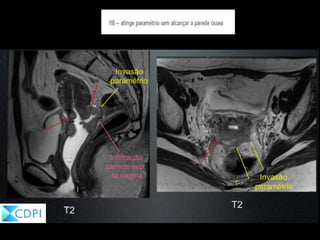

FIGO Estadiamento

- SUBESTADIAMENTO

• Avaliação difícil da invasão parametrial ( TOQUE RETAL?)

•Avaliação ineficaz do comprometimento da parede pélvica

•Ausência da avaliação de MT para linfonodos ( fator prognóstico

importante)

•Avaliação clínica subestima estadiamento cirúrgico em 15%36% dos pacientes!

• Os erros do estadiamento são de:

•28% - 1B e 50%-64% 2A – 2B (paramétrio)

Brown MA. AJR 2005;185:1221-1227